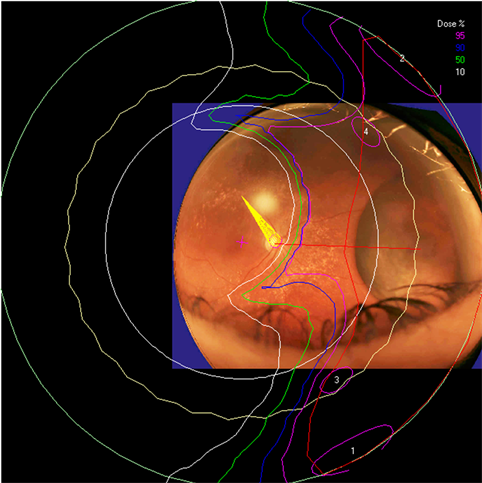

Clinical relevance of the extended distal range in silicone was studied for impact in EYEPLAN treatment planning software, including cases in which tumors were in close proximity to the optic disc/nerve and macula as well as cases in which anterior ciliary body tumors were treated. To demonstrate the necessity of the dosimetry measurement in silicone oil, we present an example of a patient with a ciliary body tumor in the right eye that is relatively amelanotic and involves the iris root but does not involve the angle. The dimension of the tumor is 13 × 8 × 8.7 mm3 (tumor height of 8.7 mm). Figure 5(a) shows the beam’s-eye-view (BEV) of the treatment plan, using gaze direction having polar and azimuth angle of (30˚, 135˚). The patient is looking towards the upper right-hand corner of the box (up and out). The range of the beam is 14.7 mm and SOBP is 16 mm. The aperture contour around the tumor represents the 50% isodose line. The optic nerve and macula are behind the tumor and receiving no proton dose, while some portion of the lens is within the 50% isodose line. This can be clearly seen from Figure 5(b) which shows the treatment plan in the lateral view. Figure 6(a) shows the dose distribution in the fundus view for a normal eye and figure 6(b) shows the dose distribution in the fundus view for a silicone oil filled eye, with adjusted proton range. Figure 7(a) and Figure 7(b) are the respective dose volume histograms (DVHs) for the two scenarios of a normal water-equivalent eye (7a) and a silicone-filled eye with potential proton range impact (7b). In this case as seen from Figure 6(a) and Figure 7(a), optic disc, macula and optic nerve gets 0 dose in the normal eye. If the eye were to be filled with silicone oil, the range of the beam would increase by 2mm. In that case as seen from Figure 6(b) and Figure 7(b), the dose to 50% area of the disc would increase by 50% of the total dose (i.e. 28 GyE in this simulation). A length of 0.4 mm of the optic nerve would receive 50% of the total dose (Figure 7(b)) as compared to the treatment plan if the eye is filled with water (Figure 7(a)). The doses to the structures of the eye in two scenarios are summarized in Table 3.

Figure 6. The isodose lines are displayed on the polar view of the back of the eye. The fundus image is superimposed on the polar view. The macula lies at the center of this view (represented by a cross), and the rest of the eye is “unfolded” around it. The optic nerve and disc are also shown near the center of the eye. The concentric circles represent the equator, ora serrata, lens and limbus of the cornea (moving from the back to the front of the eye). (a) dose distribution for normal eye (b) for eye filled with silicone oil.

The potential adjustments to distal range and penumbra in the context of silicone oil filled eyes are important for clinical eye treatment planning. The ocular melanoma case example presented in this study demonstrates that for example eyes with a thick ciliary body tumor may appear to receive zero dose to the optic nerve and disc. However once planning model modifications are made to reflect the potential impact of silicone oil on the range of the proton beam, the disc and nerve dose increase. In the silicone oil modified plan of the same eye, 50% of the area of the disc would receive 50% of the total dose and a length of 0.4 mm of the optic nerve would receive 50% of the total dose. Such clinically relevant information is essential for treatment planning, dose volume analysis, and informing the clinician and patient.